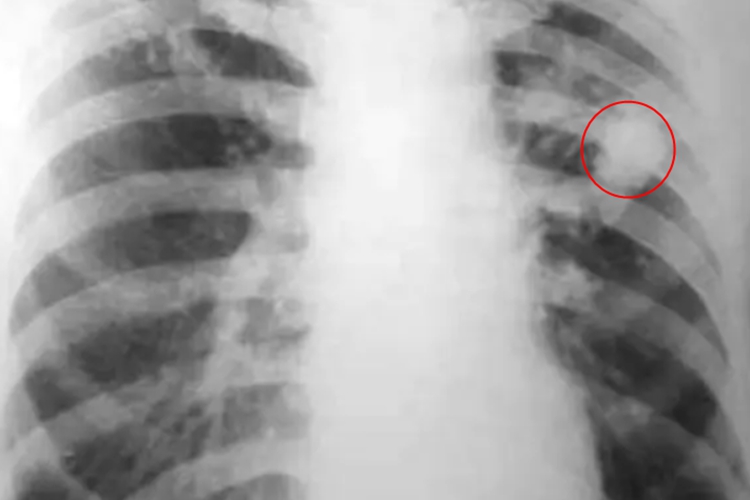

结核球表现为圆形或椭圆形密度增高的阴影,边缘较清楚,整齐、轮廓光滑,偶见较浅的分叶,一般密度均匀,病灶直径大多在2-3cm,大于5cm者少见,结核球中心的干酪灶可液化形成空洞。结核球附近可有卫星灶。